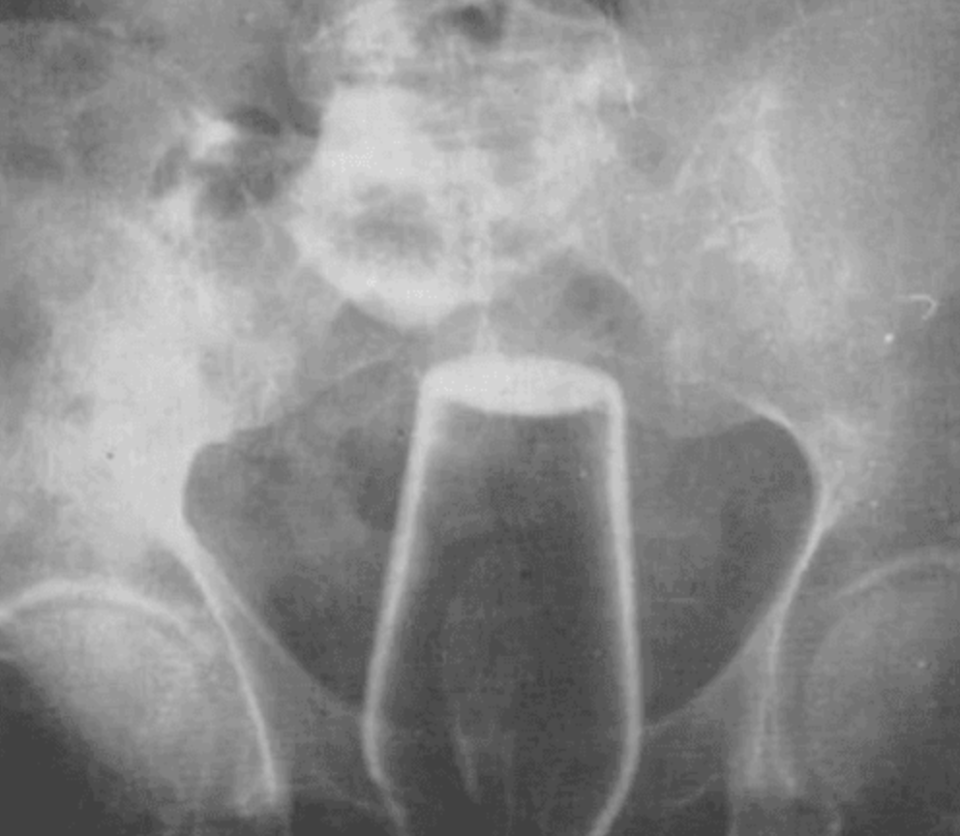

酒瓶